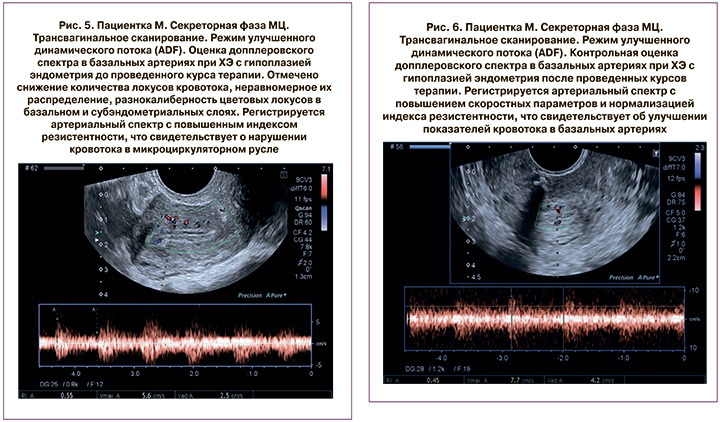

Анализ исходных сонографических данных показал, что в большинстве случаев имелись критические характеристики эндометрия и показателей кровотока в матке, характерные для ХЭ, эндомиометрита, с фиброзированием и микрокальцинозом базального слоя и субэндометриальных отделов миометрия, что отражалась и констатировалось во всех проводимых режимах и применяемых методиках исследования, особенно в показателях спектрального допплера. При допплерометрии выявились достоверное повышение сопротивления в маточных, базальных, радиальных и спиральных сосудах, увеличение систоло-диастолического отношения (S/D) и снижение конечной диастолической скорости в эндометриальных и субэндометриальных артериях (рис. 1, 3, 5).

Оценка эффективности осуществлялась путем УЗ-мониторинга с измерением ТЭ и допплерометрии кровотока матки в процессе терапии и по завершении курса лечения по вышеуказанной схеме (рис. 2, 4, 6).

На 13–15-й день следующего МЦ после проведенного лечения кавитированными растворами проводилось контрольное УЗИ органов малого таза с допплерометрией маточных сосудов, продемонстрировавшее достоверное увеличение среднего показателя М-эха до 8,7±0,9 мм. У 22/46 (47,8%) пациенток ТЭ составила 8,0–9,5 мм, у 5/46 (10,8%) пациенток – 9,6–10,5 мм, у 15/46 (32,6%) пациенток – 7,0–7,9 мм. У 4/46 (8,7%) пациенток ТЭ не изменилась относительно состояния до лечения и не превышала 6,9 мм.